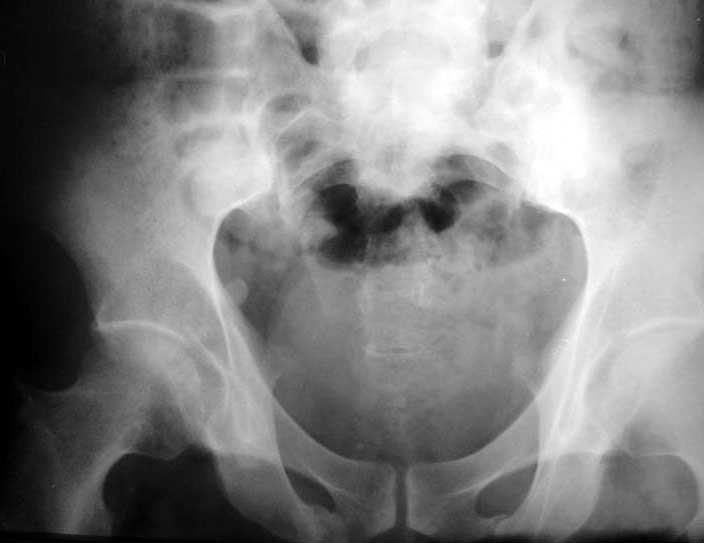

ФасInlet

Based on the CT images you provided, he appears to have a nonunion of the the right ischium, which would explain his symptoms. General principles of treatment of hypertrophic (which this appears to be) nonunions suggest rigid fixation, but I'm not sure what the best approach would be. Could get a lag screw across the fracture through a Kocher-Langenbeck approach or plate osteosynthesis through direct ischial approach, but perhaps Chip, Adam or someone with more pelvic fracture experience could enlighten us all.

I think this is just a pelvic ring disruption that has gone on to a non-union. The arrow is pointing to the inferior ramus non-union, and

the sup ramus is a high "root" fracture, right near the pecten. The sup ramus fracture enters the tab - you could call it an acetabular

fracture - but down here in Dallas we treat these acutely as stable pelvic ring injuries. The fracture in the anterior portion of the

acetabulum is so low it doesn't seem to cause much trouble.

His R sacroiliac joint is opened anteriorly a little bit - the "unreduced posterior lesion" Alex mentioned in his first post. My earlier post about plating, bone grafting, etc., is all wrong.

What you have is a pelvic fracture that hasn't healed after 4 months or so, with a minimal deformity.

I think what I would offer the guy is a percutaneous iliosacral screw to stabilize and improve the SI joint alignment, coupled with a perc anterior column screw to stabilize the high ramus fx. These screws aren't easy to place, and have a host of potential problems and complications. But, I think they would work.

Речь идёт о коплексном двустороннем повреждении таза с нарушением тазового кольца.

А именно: разрыв илио-сакрального сочленения справа, на этой же стороне трансацетабулярный перелом с незначительным смещением, перелом подвздошной кости слева. Исходя из вышеперечисленного, меня не удивляют двусторонние жалобы пациента. Однако, учитывая представленные снимки ЯМР и времени, прошедшим с момента травмы мне представляется пока преждевременным говорить об образовании ложных суставов. Судя по развиввшейся костной мозоли в области вышеперечисленных очагов, все переломы находяться в стадии консолидации. Вполне возможно, однако, что трансацетабулярный перелом приведёт в дальнейшем к развитию посттравматического артроза ТБ- сустава.

Поэтому тактику лечения я бы выбрал консервативную. Через 6 Месяцев ЯМР можно повторить. Не думаю, что транскутанная фиксация винтами приведёт к облегчению болей пациента. При подобной ситуации (см. выше) боли могут сохраняться до года.